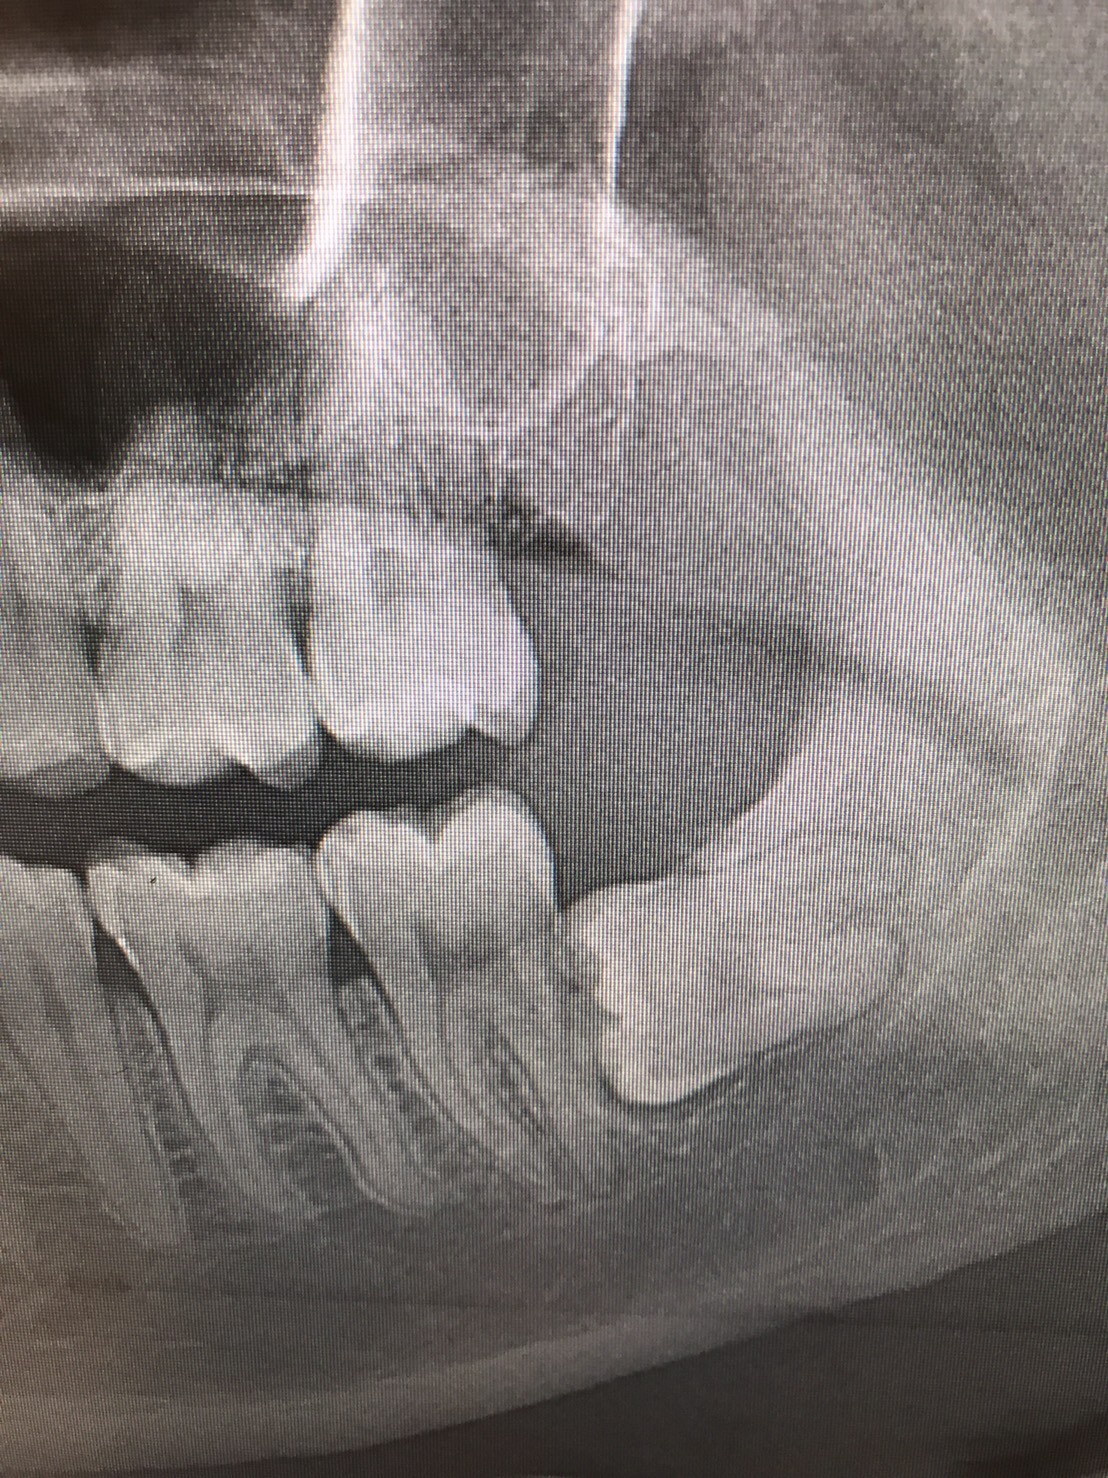

前医でインプラントの埋入角度が悪く、インプラント周囲炎になってしまった患者様の症例です。

インプラントが虫歯になることはありませんが、インプラント周囲炎というインプラントの歯周病にはなります。

インプラント周囲炎の主な原因は汚れ(菌)と力です。このように斜めに埋入されているインプラントは、真っ直ぐ埋入されているものに比べて汚れも溜まりやすく、噛む力も斜めにかかってしまうため、インプラント周囲炎になるリスクが大幅に高くなります。

この患者様は内側の骨が大幅に溶けてしまっていたので、前のインプラントを撤去して、骨を再生させると同時にインプラントを正しい位置と角度で埋入し直しました。溶けてしまっていた骨が治っていることもレントゲンでご確認いただけるかと思います。

インプラントは「どこの位置にどのような角度で入れるか」によって、一生使い続けられるかどうかの期待値が大きく異なります。値段だけを基準にクリニックを決めるのではなく、信用できる歯医医師と治療を進めることをお勧めします。